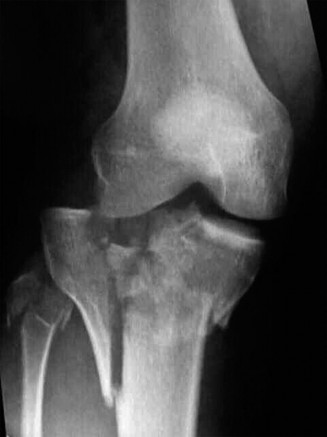

An initial trauma series of radiographs of the left knee was obtained, including standard anteroposterior, lateral, and bilateral oblique projections.

The anteroposterior radiograph demonstrated a complex, comminuted, bicondylar fracture of the proximal tibia. There was clear evidence of metaphyseal-diaphyseal dissociation, the hallmark of a Schatzker Type VI injury. The lateral tibial plateau exhibited significant articular depression and widening, characteristic of a high-energy valgus impaction force. The medial plateau demonstrated a vertical shear fracture line extending into the metaphysis, indicating a failure of the medial column.

The lateral radiograph confirmed the extensive comminution and provided a preliminary assessment of the posterior articular slope. A significant joint effusion was visible, displacing the suprapatellar fat pad. The normal anatomical posterior slope of the tibial plateau was disrupted, with evidence of posterior cortical comminution and potential posterior subluxation of the articular fragments. The oblique views further delineated the degree of articular step-off and the extent of the metaphyseal fracture lines extending distally into the tibial diaphysis.